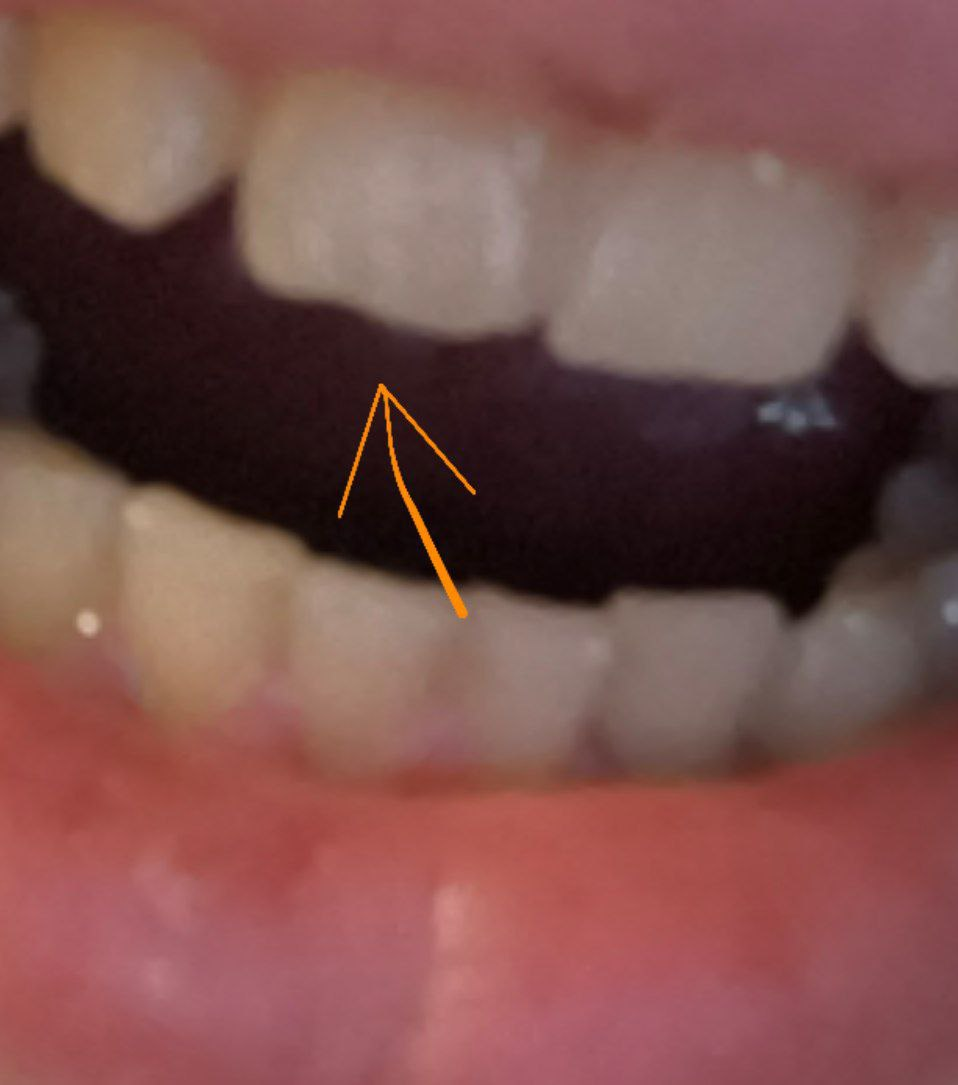

554x750

>>1631979 (OP)

Десны, на месте где зубы в них входят такая вот хуйня, отметил рядом если не понятно. Это начало парадонтита или чего-то такого? Камень года 3 не ходил чистить, каюсь. Есть связь с камнем?

Аноним 09/09/25 Втр 12:47:10 1639465 110